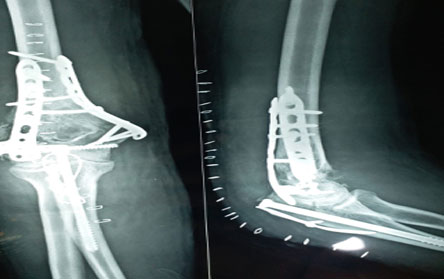

Trauma surgery:

Trauma surgery is a surgical specialty that utilizes both operative and non-operative management to treat traumatic injuries.

The Center of Orthopedics KUMAR ORTHO HOSPITAL ,Patna, offers the entire spectrum of modern orthopedic management, which is effective, patient - friendly & result oriented. In a nutshell, it is one stop treatment for all orthopedic ailments and fractures with emphasis on avoidance of complications, rapid mobilization, decreased period of confinement and an early return to normalcy.